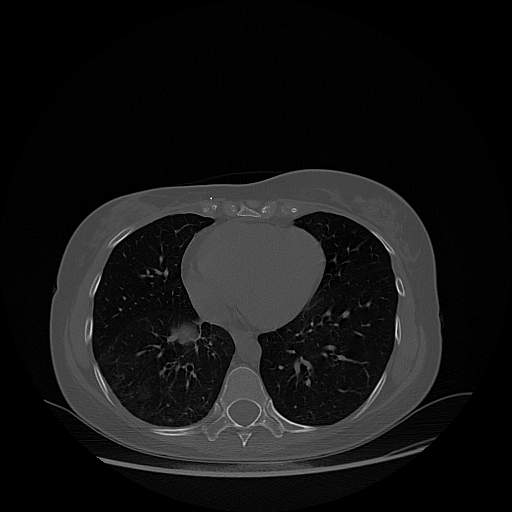

Reconstructed NATIVE CT scan (cycle consistency)

Full window (WL 1023.5, WW 4095 β†’ Low βˆ’1024, High +3071)

Lung window (WL -600, WW 1500 β†’ Low βˆ’1350, High +150)

Mediastinum window (WL 40, WW 400 β†’ Low βˆ’160, High +240)